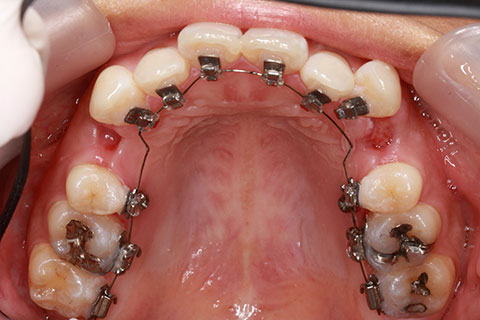

フルリンガル矯正1(上下の歯を舌側矯正で治療)

治療前

治療中

治療後

- 年齢・性別

- 33歳女性

- 治療期間

- 2年0ヶ月

- 抜歯

- 上顎4番抜歯。下顎5番欠損。

- 治療費

- 120万円(税込み)

- 備考

- フルリンガル矯正

- 治療内容

- 上顎前歯の叢生改善および下顎前歯の空隙閉鎖

- 施術の副作用(リスク)

- 装置が裏側について、目視ができないため、しっかりとブラッシングができているかどうかわかりにくい。